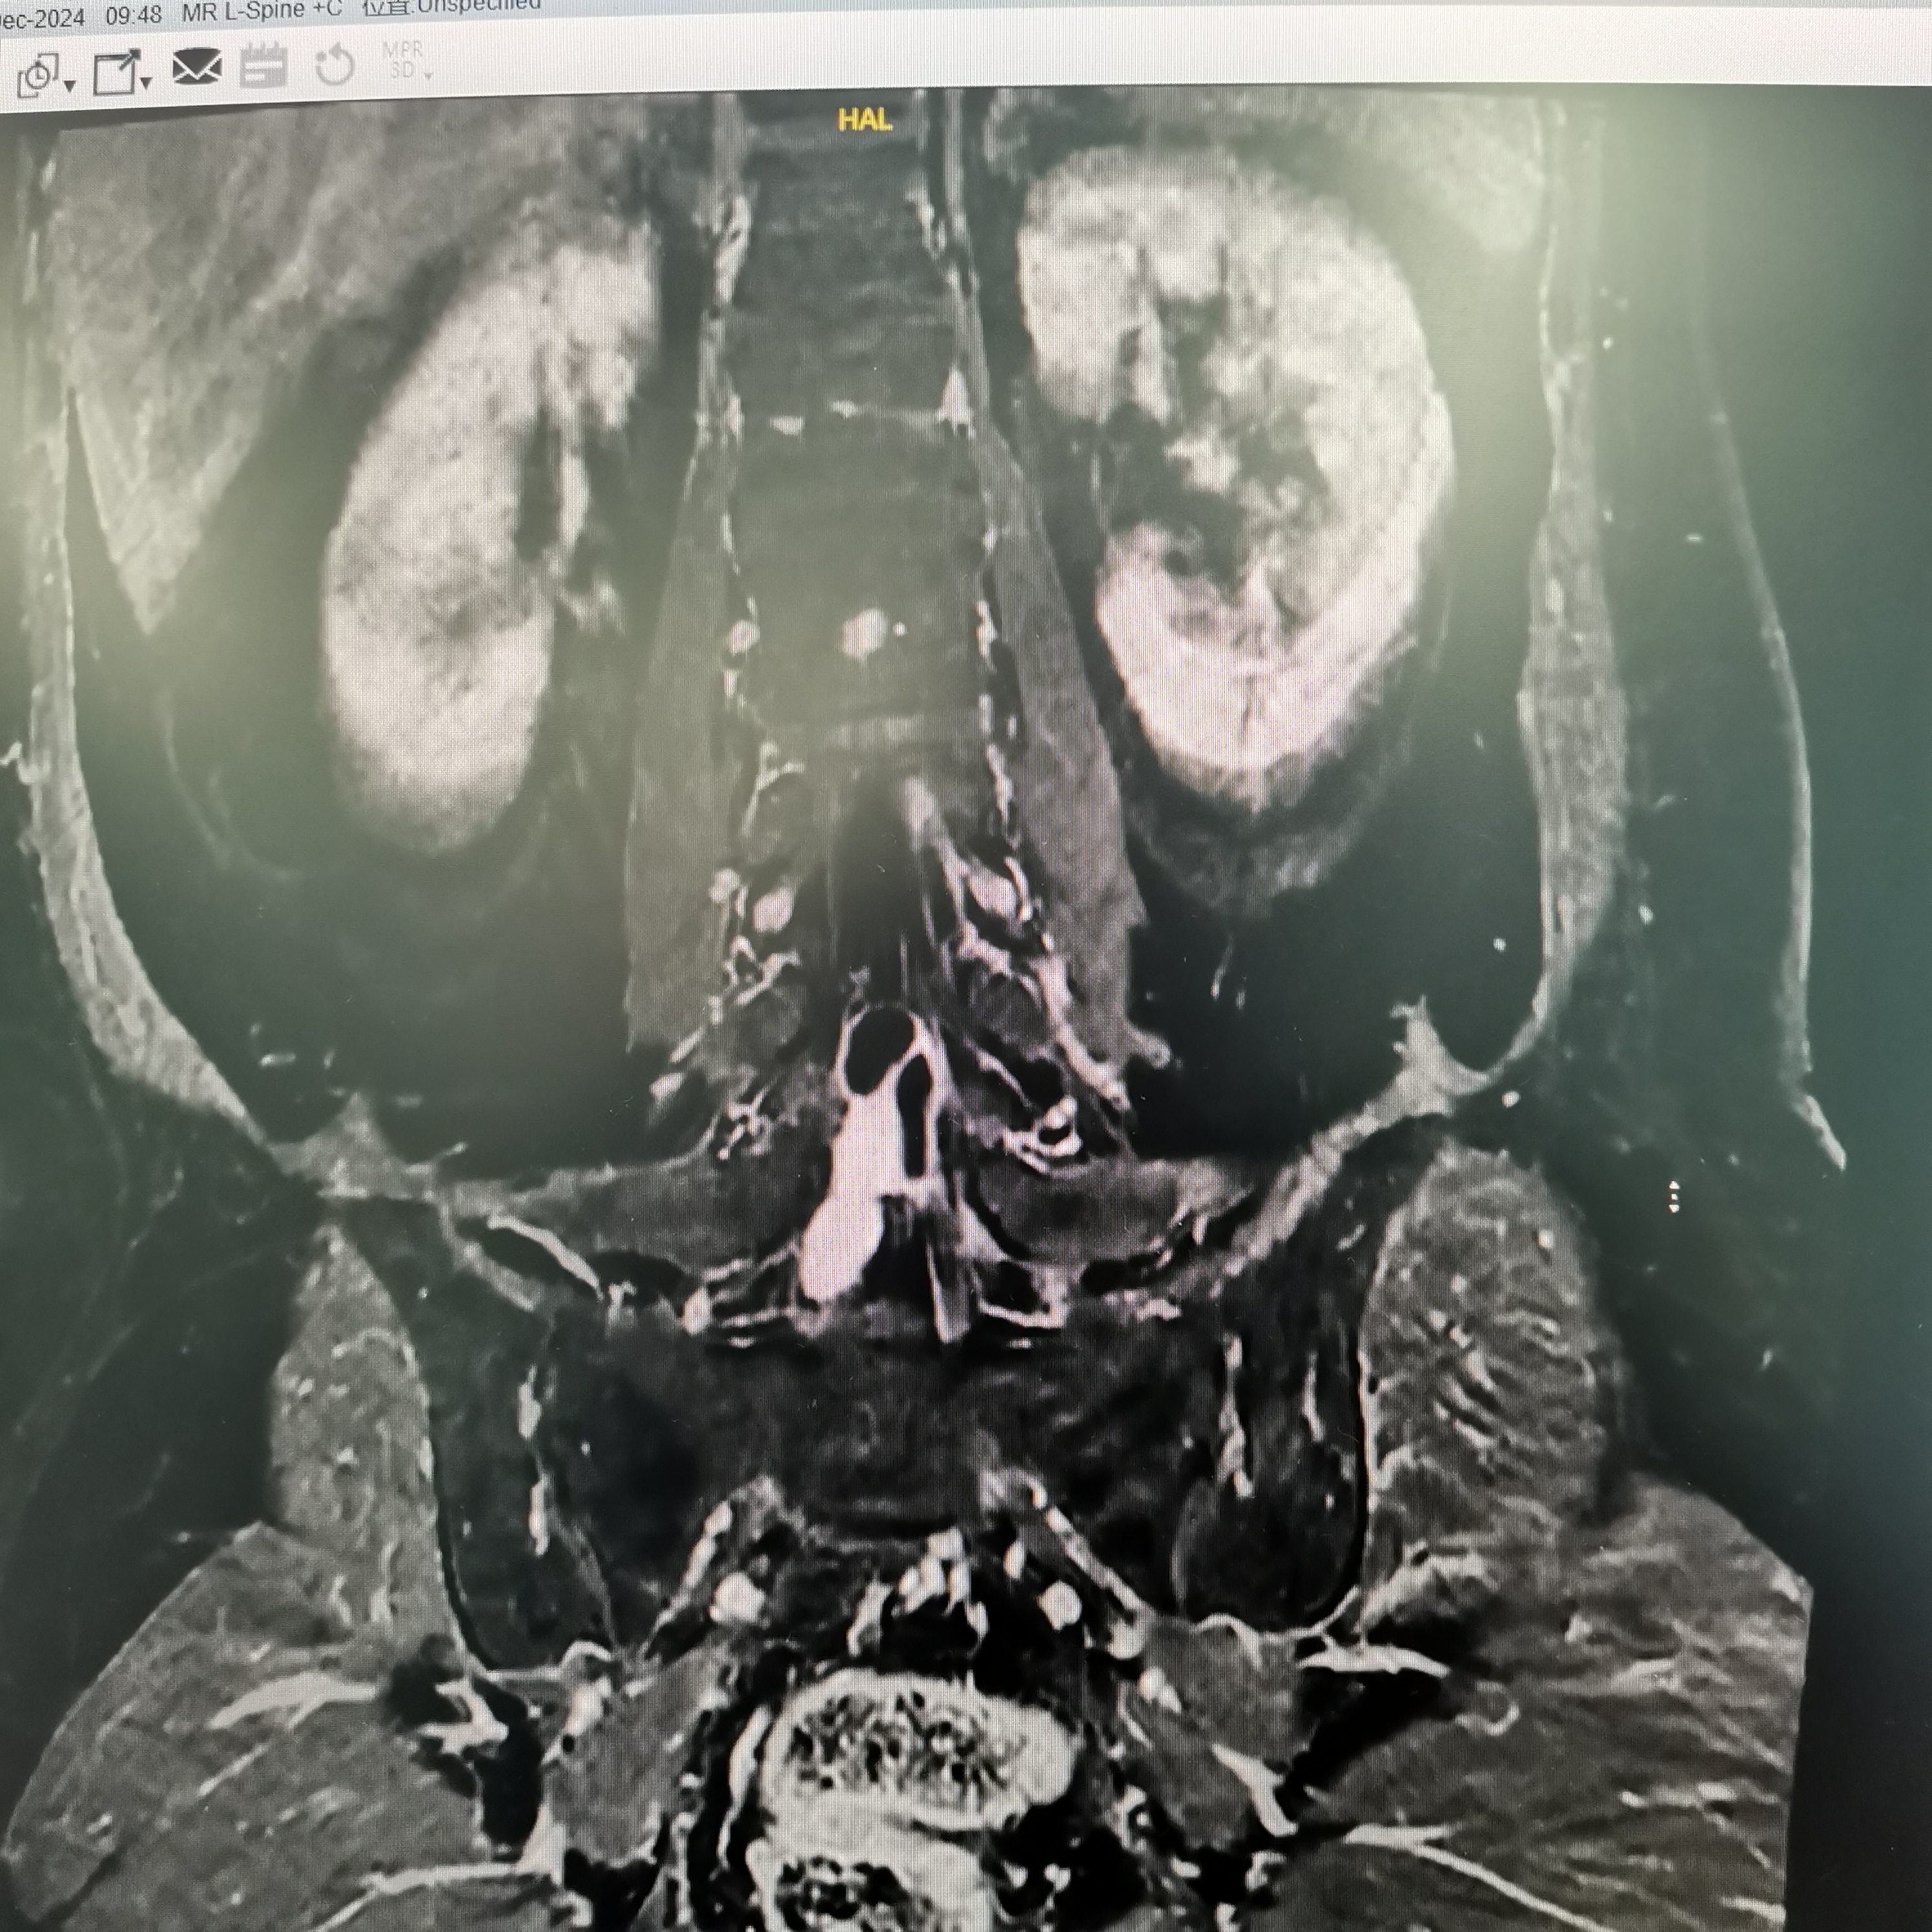

膝关节疼痛,原因是椎管内肿瘤,哑铃型生长,全切肿瘤,保留神经,疼痛症状消失…